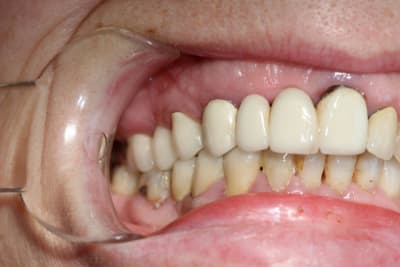

merci de votre interet; je vous édite dans l'aprèm des coupes plus grande et des photos.

tu veux absolument lui coller des implants ?

Pourquoi ne pas lui refaire couronnes et bridge antérieur de façon conventionnelle ?

C'est quoi la demande du (de la) patient(e) ?

c'est une alternative effectivement mais je ne suis pas très à l'aise avec un bridge 17-16-(15)-14-(13-12-11)-21-22-23 sachant que le support paro de 16 est merdique, 12 et 11 de bonne Richemont avec tenon cylindrique costaud : je crains donc de péter la racine de 22. La patiente n'est pas vieille et si je fais un bridge, le seul interêt sera de me laisser le temps de m'améliorer en implanto.